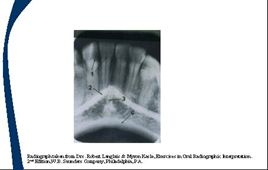

El agujero mentoniano es un espacio radiolucido justo debajo de las bicuspides mandibulares, que puede confundirse con un proceso periapical por lo que se recomienda realizar otra radiografia y si perisiste la imagen estamos ante un proceso patológico.

Linea oblicua externa, es un borde radiopaco que termina en el tercer molar.

Linea oblicua interna, o linea milohioidea, es un borde radiopaco para la insercion del musculo del mismo nombre representado en la imagen por la letra Y.